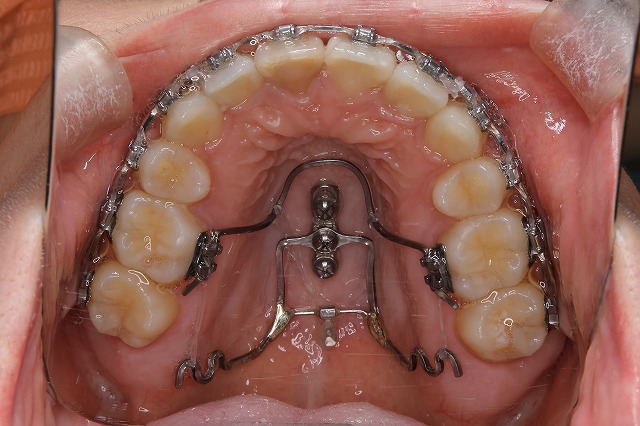

アイステーションは、上あごの真ん中(口蓋)に小さなスクリューを埋め込む矯正装置です。

このスクリューを支点にして、歯を引っ張ったり押したりすることで、ワイヤーだけでは難しかった立体的な歯の移動可能にします。

・2本のスクリュー

・専用のアーム

を組み合わせることで、歯を前後・左右・上下のあらゆる方向にコントロールできます❕